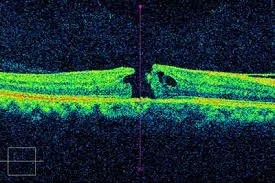

OCT is a cutting-edge, non-invasive imaging technology that uses light waves to capture detailed, cross-sectional images of the retina, the delicate tissue lining the back of the eye. It allows ophthalmologists to see each layer of the retina in extraordinary detail, making it possible to detect early signs of blinding conditions such as macular degeneration, diabetic retinopathy, retinal vein occlusion, and glaucoma. In surgical care, OCT is equally essential for monitoring patients before and after retina or cataract surgery, ensuring that treatment is both precise and effective.